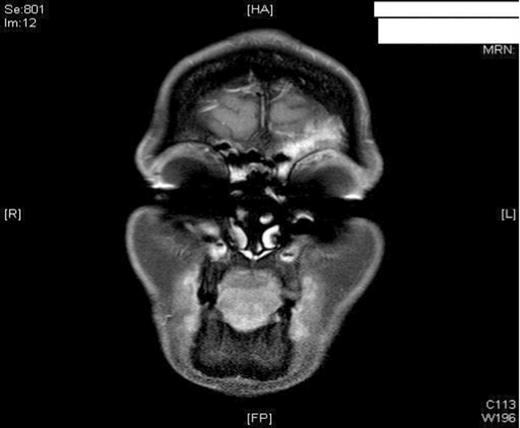

The patient had an uneventful post-operative period and remained pain-free with no residual swelling of the forehead. She was discharged home 24 hours post-operatively with FlixonaseTM Nasules for 6 weeks, SterimarTM spray for 2 months and regular steam inhalations. At 6 months post-op, the patient remained asymptomatic and well. To avoid any unnecessary radiation, the patient was assessed with MRI imaging. As shown, the imaging revealed no complications and showed adequate resolution of the mucocele (Figure 3).

MRI imaging (a) coronal (b) axial views post procedure revealing resolution of the mucocele and no intracranial or orbital complications (see figure 1).